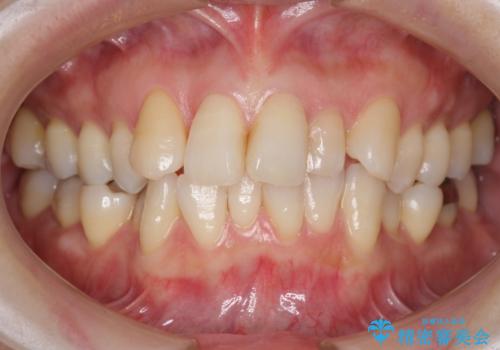

- 右上の前歯が内側に入っているのを気にして来院。

右上の奥歯を後ろに移動して、前に出すスペースを確保してから並べました。

前歯が内側に入っていると、笑った時にそこが黒くなり、歯が抜けたように見えます。

口を開けたとき、笑顔の印象が大きく変わり、大変喜んでいただけました。